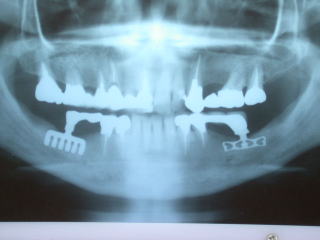

上の奥歯の例です。

上は上顎洞という骨空洞があり、インプラントの植立が困難な場合が多いです。

こちらのケースは左上の保険外延長ブリッジのロウ着部分が破損のためインプラントを入れて3歯連続冠にしました。